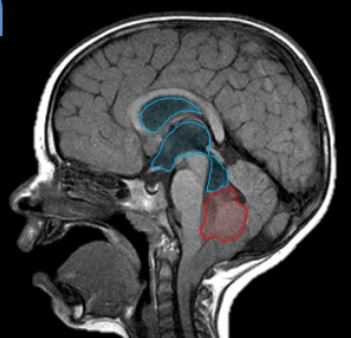

![эпендимома]()

МРТ головного мозга.Т1-взвешенная сагиттальная МРТ. Типичные локализации эпендимомы.

Эпендимома составляет 2-9% от внутричерепных опухолей и 6% от глиом. Из эпендимальных опухолей у взрослых встречается субэпендимома. Она составляет около 8% от эпендимальных опухолей и располагается у стенки желудочка. Пики частоты собственно эпендимомы приходится на возраст 5 лет и 34 года. Опухоль происходит из эпендимоцитов. Обычно это доброкачественные формы. В 60-70% случаев опухоль локализуется инфратенториально в области IV желудочка и в 5-8% в полушариях мозжечка. Гораздо реже обнаруживается супратенториальная локализация эпендимомы: в полушариях вблизи желудочков (на корональных срезах по виду напоминает “цветную капусту”), в области III желудочка, четверохолмия или мосто-мозжечковом углу. Доброкачественные эпендимомы имеют экспансивный тип роста. Внутренняя структура при МРТ неоднородная в связи с кистами (43-83% случаев) и кальцификацией (50% случаев). Контрастное усиление при МРТ наблюдается в трети случаев. Анапластическая эпендимома (градация III) метастазирует по ликворным путям.

Инфратенториальные эпендимомы у взрослых встречаются гораздо реже, чем у детей. Эпендимома встречается в области IV желудочка. Она имеет солидный и кистозный компоненты. При МРТ головного мозга их внутренняя структура часто неоднородная за счёт кальцинатов, кист, гемоглобина и гемосидерина, а также внутриопухолевых сосудов. Эпендимомы часто распространяются через отверстия Лушка и Маженди, что видно при МРТ в корональной плоскости. профессор Холин А.В. имеет большой опыт МРТ в СПб диагностики внутрижелудочковых опухолей мозга в том числе и на открытом МРТ. Среди центров МРТ СПб мы имеем огромный опыт МРТ выявления разных опухолей головного мозга.